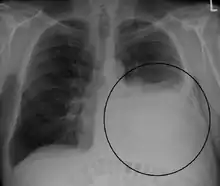

Pleural effusion Anteroposterior Chest X-ray of a pleural effusion. The A arrow shows fluid layering in the right pleural cavity. The B arrow shows the normal width of the lung in the cavity

A large left-sided pleural effusion as seen on an upright chest X-ray

Imaging

A pleural effusion appears as an area of whiteness on a standard posteroanterior chest X-ray.[12] Normally, the space between the visceral pleura and the parietal pleura cannot be seen. A pleural effusion infiltrates the space between these layers. Because the pleural effusion has a density similar to water, it can be seen on radiographs. Since the effusion has greater density than the rest of the lung, it gravitates towards the lower portions of the pleural cavity. The pleural effusion behaves according to basic fluid dynamics, conforming to the shape of pleural space, which is determined by the lung and chest wall. If the pleural space contains both air and fluid, then an air-fluid level that is horizontal will be present, instead of conforming to the lung space.[13] Chest radiographs in the lateral decubitus position (with the patient lying on the side of the pleural effusion) are more sensitive and can detect as little as 50 mL of fluid. Between 250 to 600mL of fluid must be present before upright chest X-rays can detect a pleural effusion (e.g., blunted costophrenic angles).[14]